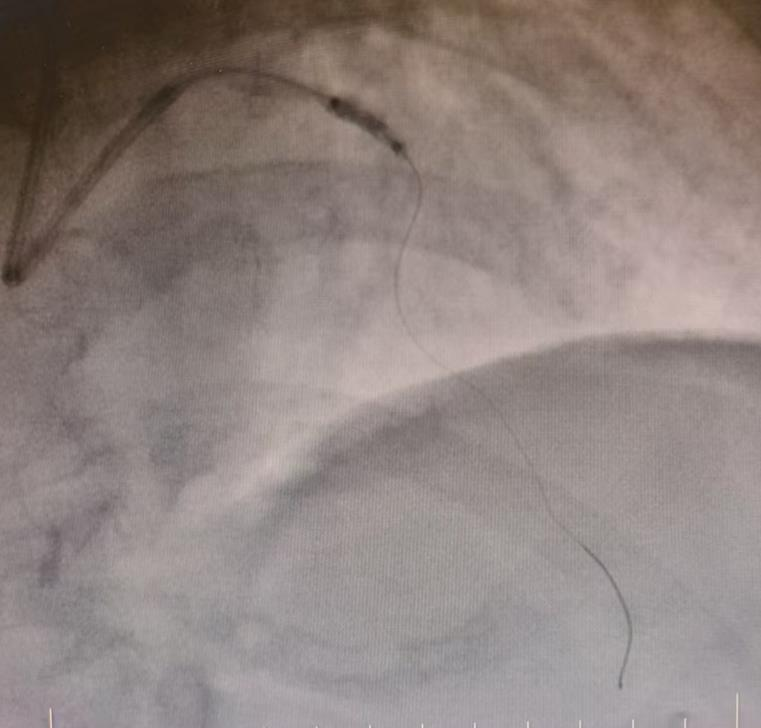

决胜一击:精准植入支架生命通道恢复畅通

经过这两步精妙的预处理,原本坚硬的病变血管变得“顺从”。手术团队顺势而为,依次将药物洗脱支架精准植入到病变位置,并通过后扩张使其完美贴合血管壁。术后造影显示,患者前降支血流通畅,支架膨胀理想,手术取得圆满成功。

术后造影